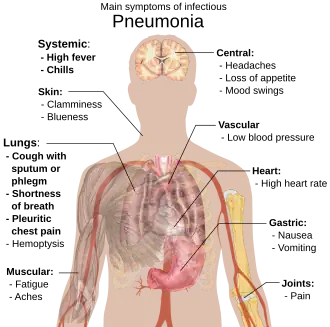

Signs and symptoms

People with infectious pneumonia often have a productive cough, fever accompanied by shaking chills, shortness of breath, sharp or stabbing chest pain during deep breaths, and an increased rate of breathing.[9] In elderly people, confusion may be the most prominent sign.[9]

The typical signs and symptoms in children under five are fever, cough, and fast or difficult breathing.[23] Fever is not very specific, as it occurs in many other common illnesses and may be absent in those with severe disease, malnutrition or in the elderly. In addition, a cough is frequently absent in children less than 2 months old.[23] More severe signs and symptoms in children may include blue-tinged skin, unwillingness to drink, convulsions, ongoing vomiting, extremes of temperature, or a decreased level of consciousness.[23][24]

Bacterial and viral cases of pneumonia usually result in similar symptoms.[25] Some causes are associated with classic, but non-specific, clinical characteristics. Pneumonia caused by Legionella may occur with abdominal pain, diarrhea, or confusion.[26] Pneumonia caused by Streptococcus pneumoniae is associated with rusty colored sputum.[27] Pneumonia caused by Klebsiella may have bloody sputum often described as "currant jelly".[28] Bloody sputum (known as hemoptysis) may also occur with tuberculosis, Gram-negative pneumonia, lung abscesses and more commonly acute bronchitis.[24] Pneumonia caused by Mycoplasma pneumoniae may occur in association with swelling of the lymph nodes in the neck, joint pain, or a middle ear infection.[24] Viral pneumonia presents more commonly with wheezing than bacterial pneumonia.[25] Pneumonia was historically divided into "typical" and "atypical" based on the belief that the presentation predicted the underlying cause.[29] However, evidence has not supported this distinction, therefore it is no longer emphasized.[29]